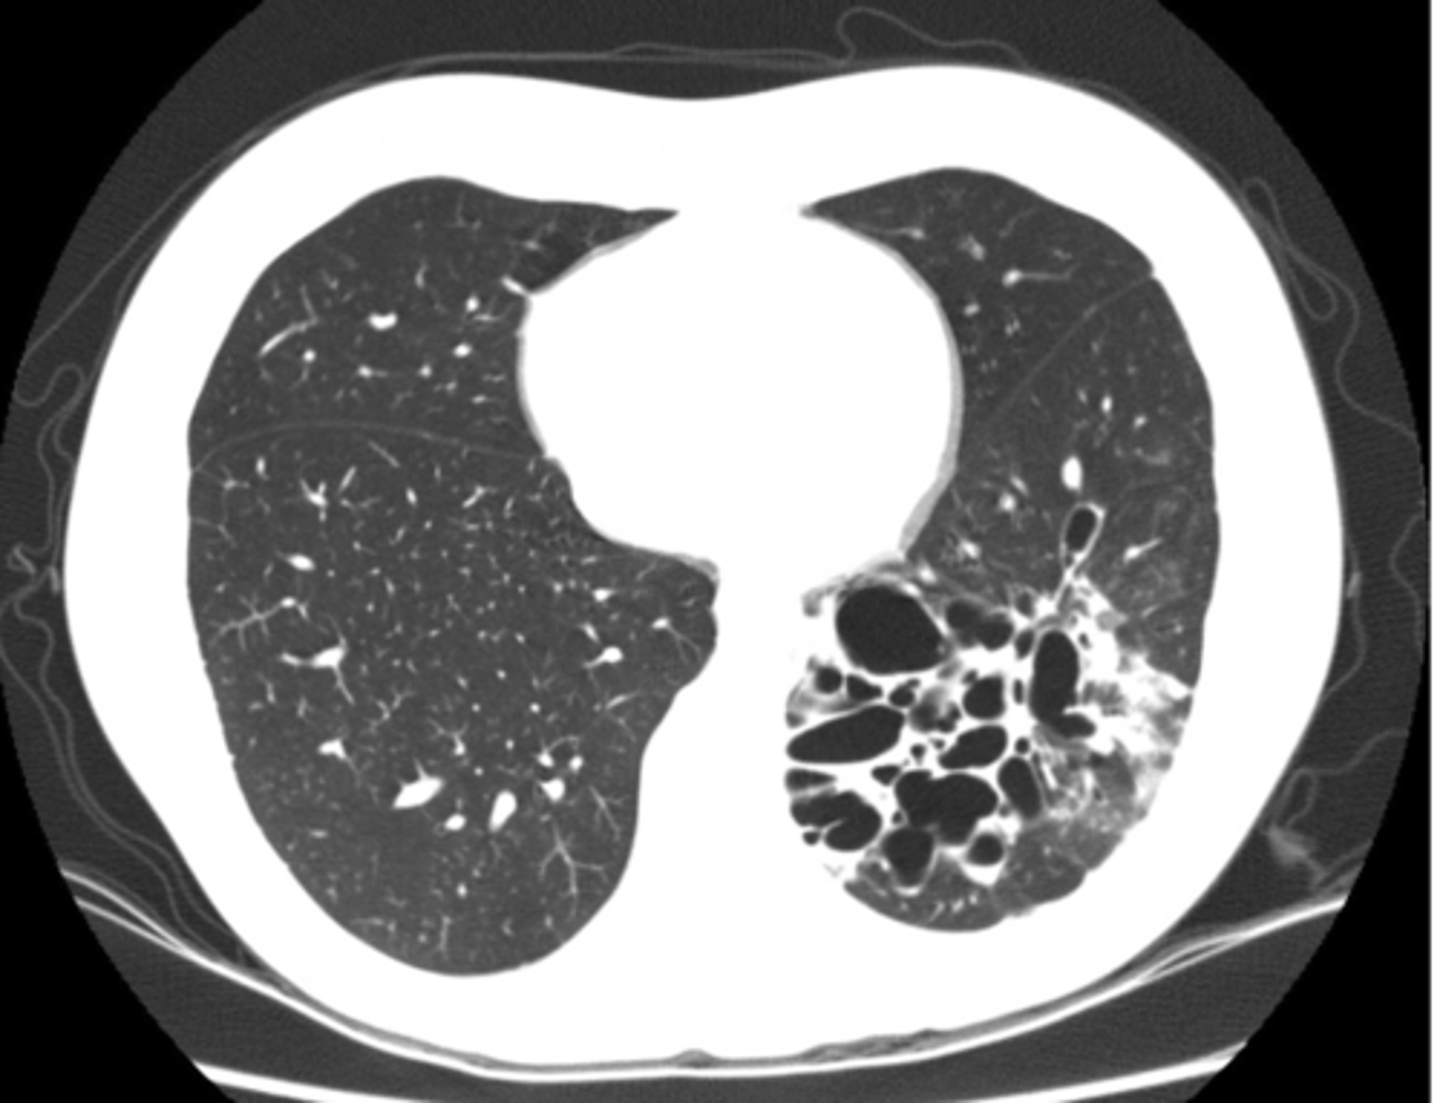

bronchiectasis

Dx

<p>Dx</p>